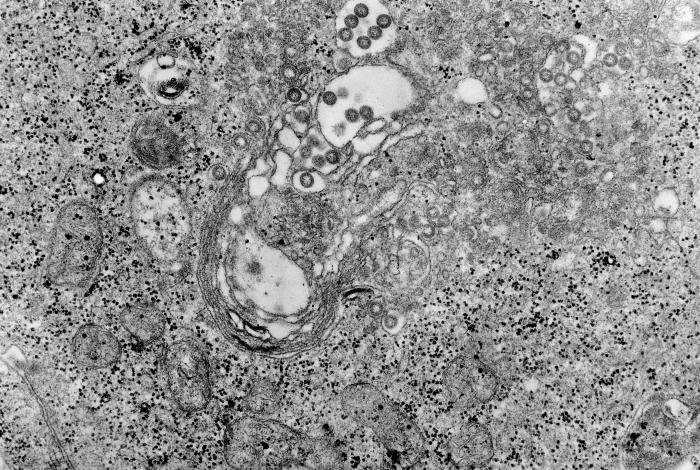

Tecido da febre do Vale do Rift. Crédito: Domínio Público

A febre do Vale do Rift é uma zoonose (uma doença que afeta animais e pode ser transmitida aos humanos). É causada pelo vírus RVF, um flebovírus da família Phenuiviridae (ordem Bunyavirales). A doença afecta principalmente animais domésticos, principalmente bovinos, ovinos e caprinos, mas também camelídeos e outros pequenos ruminantes. Ocasionalmente, pode infectar humanos.